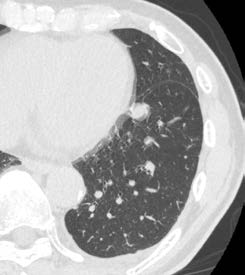

CLEAR Motion(図2)などで

質の高い検査を迅速に提供

CLEAR Motionについては、CardiacとBodyの両方で使用している。稲垣係長は、「大動脈解離を疑い、従来であれば心電図同期が必要な症例でも、Aquilion ONE / INSIGHT Editionではガントリの回転速度やヘリカルスキャンも高速化していることに加えて、CLEAR Motionをかけることで心拍動によるアーチファクトを抑えて、ブレのない画像が得られます。スループットも向上しており、患者さんにとっても有用な検査が提供できます」と評価する。

Aquilion ONE / INSIGHT Edition+Abierto Visionによる臨床画像

CLEAR Motion OFF + Hybrid-IR CLEAR Motion OFF + Hybrid-IR

CLEAR Motion OFF + DLR CLEAR Motion OFF + DLR

CLEAR Motion ON + PIQE CLEAR Motion ON + PIQE

図2 原発性肺がん、肺転移症例で経過観察中

PIQE+ CLEAR Motionの併用で、心拍動に伴うアーチファクトを低減し、

高い時間分解能かつ高精細画像の両立が期待できる。